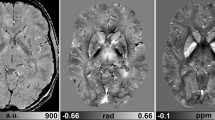

Calcification can be differentiated from hemorrhage based on differences in susceptibility effects – calcium is diamagnetic and blood products show largely paramagnetic susceptibility [6–9] (Fig. 1). This makes MR comparable to computed tomography (CT) in calcium imaging. However, one has to be very careful in inferring magnetic properties from visual image information since the phase patterns associated with these lesions are not only dependent on the susceptibility difference between tissues but also on the geometry of the lesion [10]. MinIP and filtered phase images of the midbrain (Fig. 2a, b) are able to clearly show mineralization of the red nucleus and the substantia nigra. Dentate nucleus mineralization is also best visualized in SWI images (Fig. 2c, d). Mineralization, iron and hemorrhage in the basal ganglia are also clearly visualized on phase images (Fig. 2e, f, 14). This may be useful in demonstrating and quantifying mineral deposition in various degenerative brain diseases.

Mineralizing microangiopathy in a young male patient. a Axial 7-mm-thick non-contrast, enhanced computed tomography (NECT) image showing the calcifications. b High-resolution T2 turbo spin echo (TSE) (TR/TE/TA = 5260 ms/106 ms/3.42 min, matrix = 384 × 384, nex = 4) demonstrating the ‘U’-shaped cortical calcifications in the depth of the sulcus (arrow). c–e Susceptibility-weighted imaging (SWI) – magnitude, phase and minimal intensity projection (minIP) images, respectively. The lesions are hypointense in all the images, suggesting diamagnetic susceptibility due to calcification (see text). Note also the detailed cerebral venous anatomy visualized in the minIP images (e)